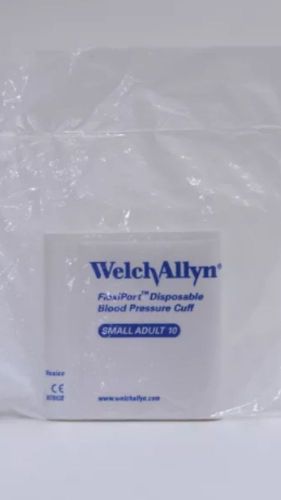

Welch Allyn Flexiport Disposable Blood Pressure Cuff Small Adult 10